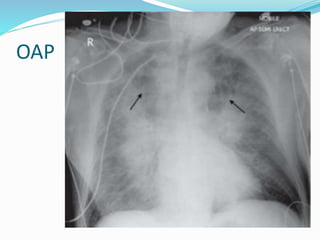

OAP

 Cardiomégalie et opacités interstitielles ou alvéolaires

(oedème pulmonaire).

Cardiomégalie (OAP)